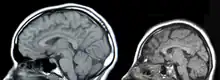

In mammals, including humans, mutations to the tRNA-intron lyase gene are associated with neurodegenerative diseases such as Pontocerebellar Hypoplasias (PCH). This disease leads to atrophy of the cerebellum and pons. This causes microcephaly, severe motor impairment, and severe mental impairment.

Pontocerebellar hypoplasias (PCH) are a group of neurodegenerative disorders that include atrophy of the cerebellum and pons, microcephaly, severe motor impairment, and severe mental impairment.[19] There are five subtypes of PCH, two of which (PCH2 and PCH4) are linked to mutations in eukaryotic tRNA-intron lyase.[19] PCH2 is associated with symptoms of dystonia and spasticity, while PCH4 is associated with early lethality and a more severe course of disease.[19]

The most common mutation found in patients with PCH2 and PCH4 is a 919G>T mutation in the TSen54 subunit, leading to a substitution at position 307 of alanine by serine.[20] This mutation causes destabilization of the β-β-interaction, altering the ability to form the heterotetramer.[20] The development of PCH from this destabilization is not well understood, but it is thought to be the result of neuronal sensitivity to changes in tRNA levels.[20] Many neuronal diseases result from changes in tRNA and mRNA processing, and this TSen54 subunit mutation may disrupt the tRNA processing pathway.[20]

Other causes of PCH2 and/or PCH4 include other TSen54 point mutations (Q246X, Q343X, S93P), mutations on TSen34 (R58W), and mutations on TSen2 (Y309C).[19] TSen15 was also identified as a potential cause for PCH2, with pathogenic mutations affecting Trp76, His116, and Tyr152.[21]